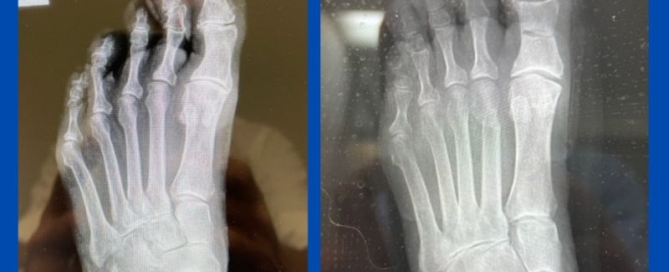

Minimally invasive forefoot reconstruction

Blog's main page There have been many advances in foot surgery over the years, with minimally invasive surgery (MIS) or keyhole surgery being one such modality. The below before and [...]